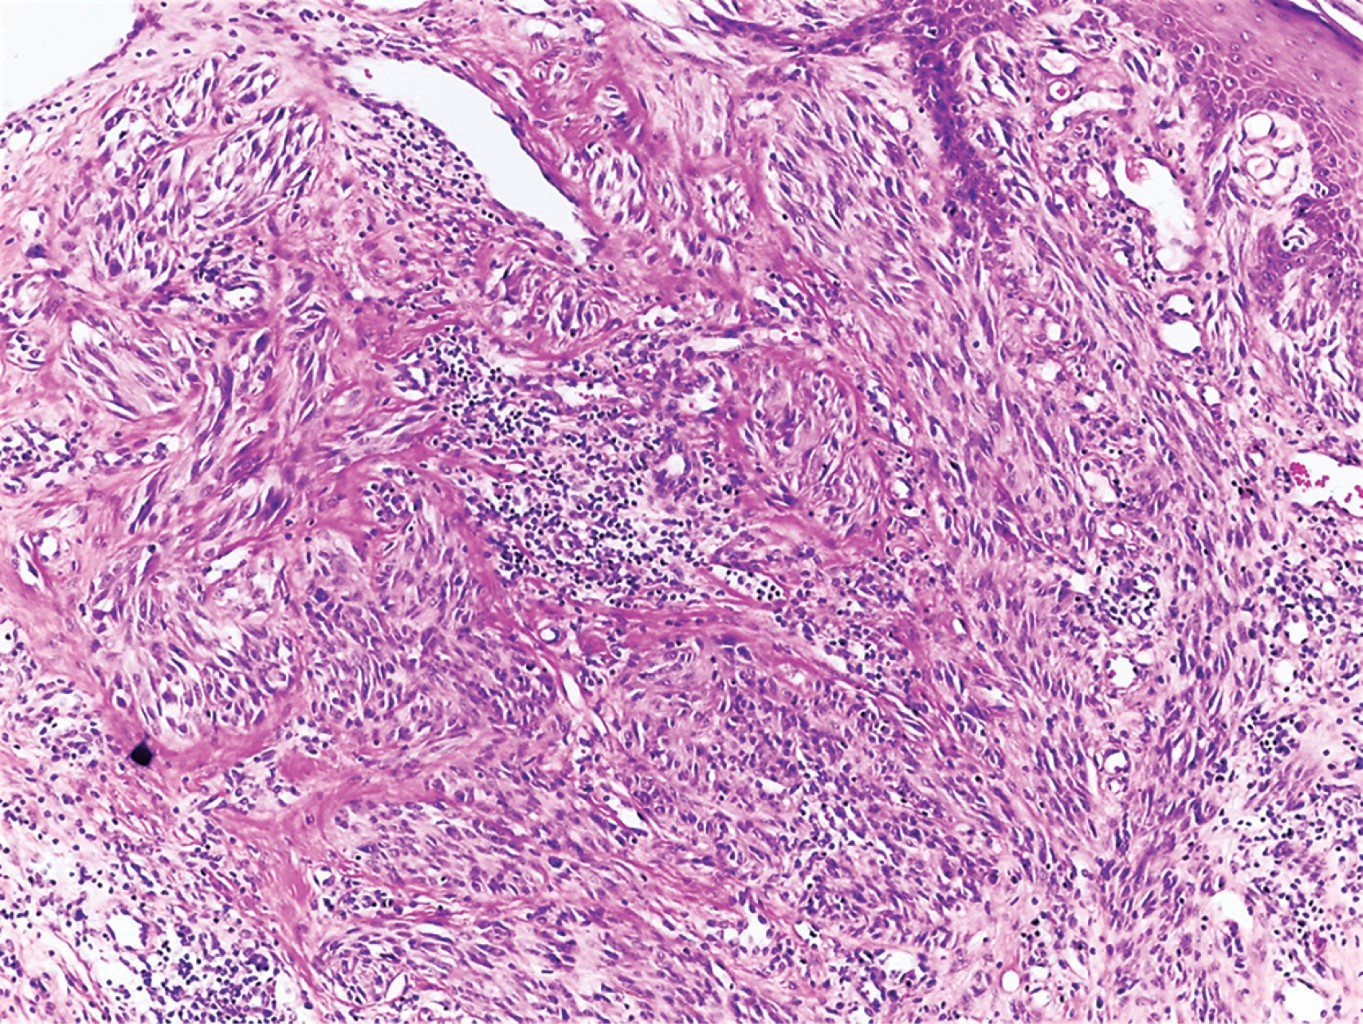

En la histopatología se encuentra un nevo de unión, intradérmico o compuesto, con la presencia de melanocitos epitelioides o fusiformes dispuestos en nidos en la base de crestas alargadas y epidermis hiperplásica. Los melanocitos dentro de los nidos tienen orientación vertical, con mitosis mínima o ausente en la dermis profunda.

Con los datos anteriores se diagnostica granuloma piógeno, por lo que se efectúa rasurado de la lesión y se envía al Servicio de Dermatopatología, en donde se reporta nevo de Spitz con extirpación incompleta, con la siguiente descripción histopatológica: los cortes muestran neoformación exofítica cuya epidermis presenta hiperqueratosis, grandes tapones córneos y zonas con aplanamiento de los procesos interpapilares. En el espesor de la dermis se observan melanocitos de aspecto epitelioide y fusiformes que tienden a formar nidos y están inmersos en un estroma fibroso (Figuras 2, 3 y 4).

Figura 3

Figura 4